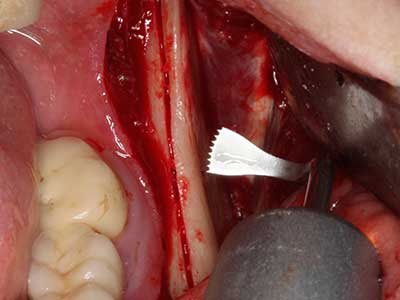

Sollen chirurgische Eingriffe mit unmittelbarer Knochenbeziehung an empfindlichen Strukturen wie Blutgefäßen oder Nerven erfolgen, so bergen rotierende Instrumente ein erhebliches Potential an iatrogener Schädigung. Gerade bei Nervdarstellungen nach iatrogener Schädigung, oder aber im Zuge einer Nervlateralisation für resektive und rekonstruktive Eingriffe oder Implantatinsertionen können piezoelektronische Geräte hilfreich sein Knochendeckel zu präparieren und nervnahe Hartgewebsanteile zu entfernen (Abb. 17-20). Ein leichter Kontakt des Nervstrangs zur Piezospitze bleibt dabei in der Regel folgenlos – allerdings kann eine unvorsichtige Vorgehensweise mit sägeartigen Bewegungen bzw. Ansätzen bei noch vorhandener knöcherner Unterlage durchaus temporäre oder aber auch permanente Nervschädigungen verursachen. Das Risiko einer solchen Schädigung wird jedoch als wesentliche geringer eingeschätzt als unter Anwendung von Säge- oder Fräsinstrumenten (Pereira, Gealh et al. 2014).